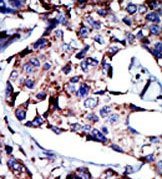

Supportive validation

- Submitted by

- OriGene (provider)

- Main image

- Experimental details

- Formalin-fixed and paraffin-embedded human cancer tissue reacted with the primary antibody, which was peroxidase-conjugated to the secondary antibody, followed by DAB staining.

- Validation comment

- IHC